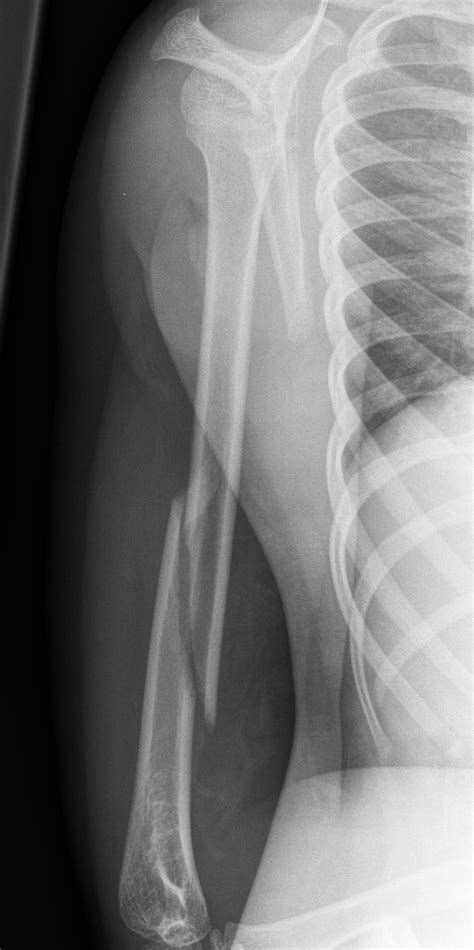

Distal humerus fractures | PPTX